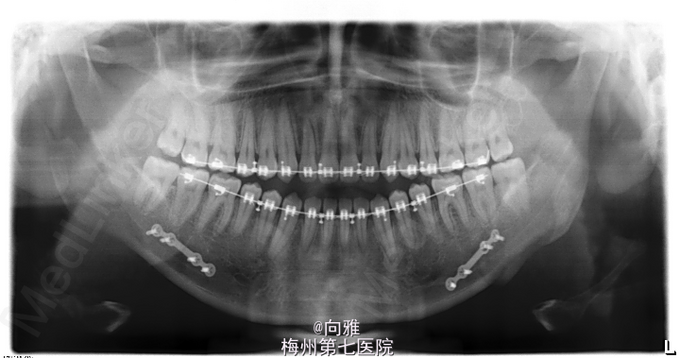

青年男患者,下颌前突十余年,患者于十年余前无明显诱因出现上颌后缩,下颌前突,影响美观及咬合,逐渐加重,未行处理,1年前于我院正畸科就诊,制定“正畸-正颌联合”治疗方案,遂行正畸治疗,现已完善术前正畸,今为行正颌手术入院治疗

1.下颌前突 2.偏颌畸形,全麻下行BSSRO后退术+双侧下颌骨去骨皮质术+坚固内固定术

口内缝线待其自然脱落;继续行颌间弹性牵引,继续至正畸科复诊,术后护理很重要